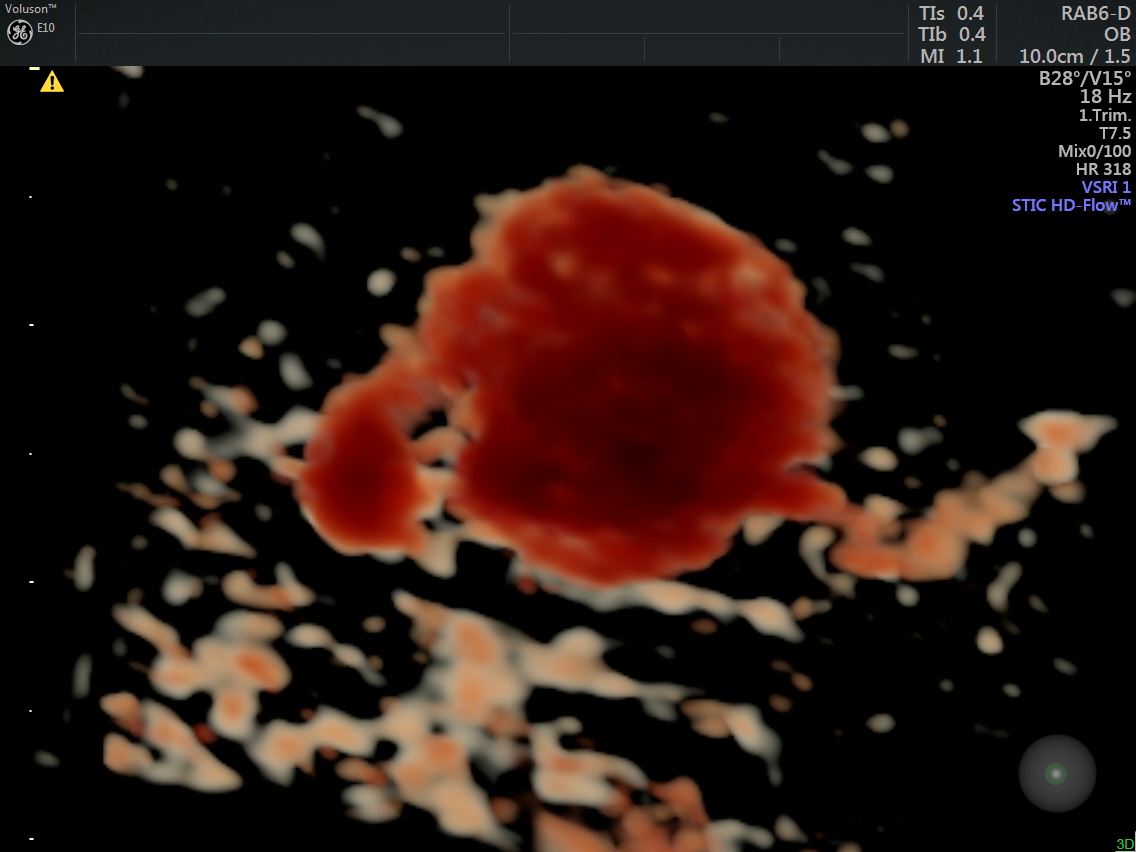

A prominent globular vascular structure of size 1.71 + 1.28 cms was seen in the right lobe.

The red globular structure seen in colour flow was striking.

A small feeding vessel leading from the portal vein entering the vascular structure is seen.

The venous flow is established by power doppler in the following pictures.